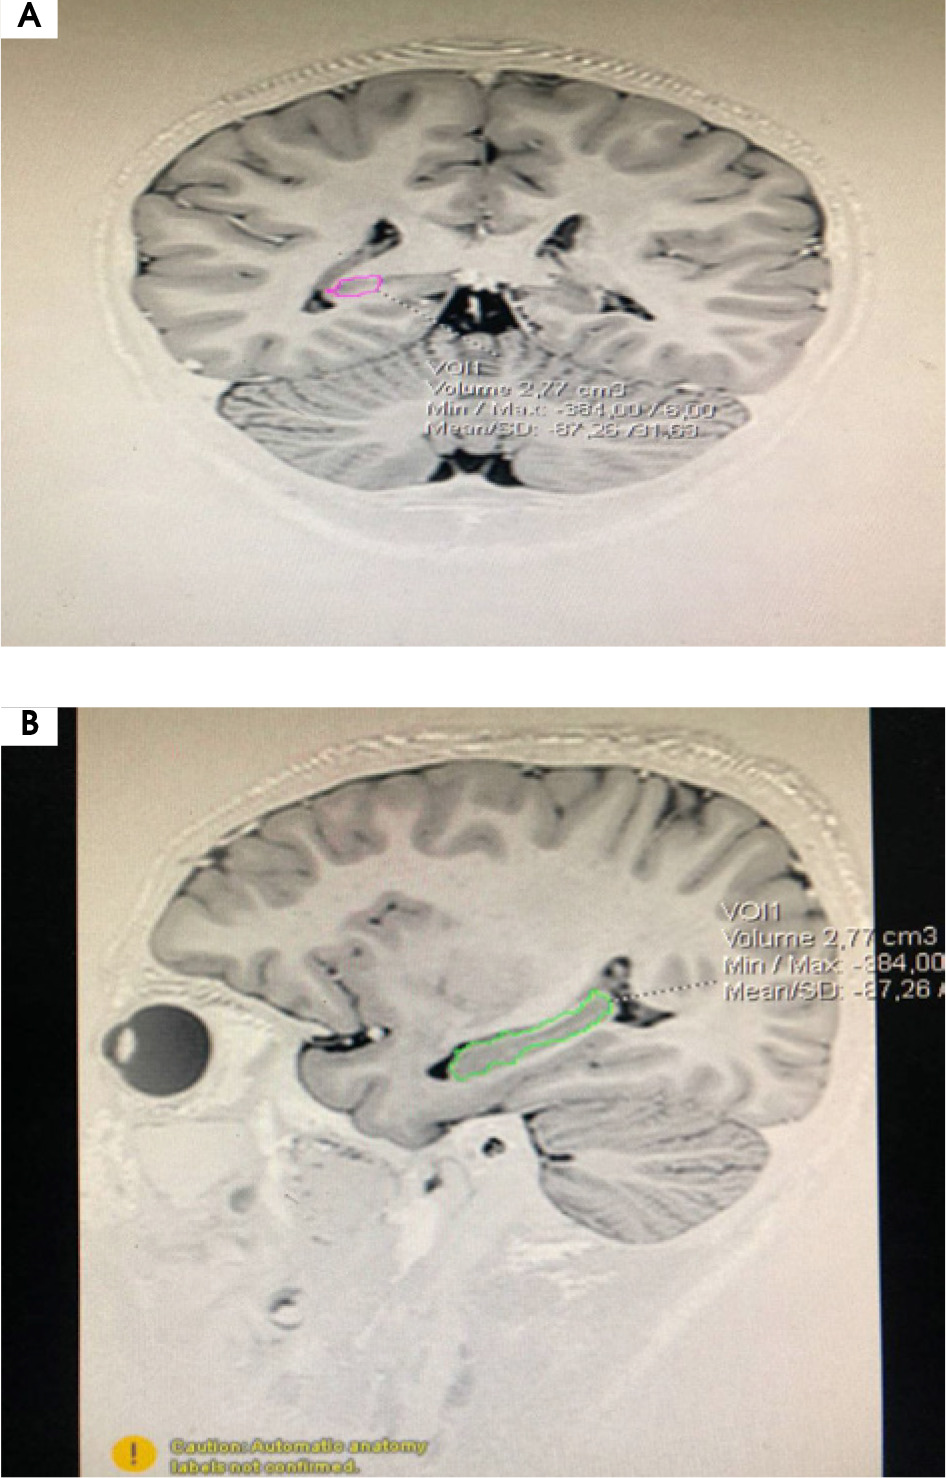

Figure II

Magnetic resonance imaging showed bilateral hippocampal sclerosis with decreased volume of both hippocampi

The patient’s vital signs were within normal limits. On examination, he showed an involuntary movement that met the criteria for motor tics followed by vocal tics (hiccups). To exclude metabolic disorders, we performed laboratory tests such as complete blood count, renal function test, liver function test, and electrolyte concentrations; all were within normal limits. Electroencephalography showed a generalized diffuse slowing of brain activity with a frequency of 5-6 Hz, suggesting generalized mild encephalopathy (Figure I). A contrast-enhanced head MRI showed bilateral hippocampal sclerosis with decreased hippocampal volume (Figure II).

Diagnosis is made by observation of clinical signs and is supported by the presence of a comorbid behavioral disorder. The result of neurological examination is usually normal, and only tics are found. Computed tomography (CT) scans of the head and MRI are usually normal. However, there is evidence of structural changes in the limbic structures (such as the amygdala and hippocampus) on some MRIs for their functional roles on the CSTC circuit. This patient’s MRI showed a reduced volume of the bilateral hippocampus, which explained his learning disability [10]. This patient’s MRI also showed bilateral hippocampal sclerosis. Hippocampal sclerosis (HS) is the most frequent histopathology found in patients with temporal lobe epilepsy (TLE) [11]. The causes of HS are still controversial and likely multifactorial, such as prolonged febrile seizures (FS). A FEBSTAT study suggests that children with pro-longed FS may have acute hippocampal injury and an increased frequency of hippocampal developmental change. Several family studies have provided some evidence for a genetic predisposition to HS [12].